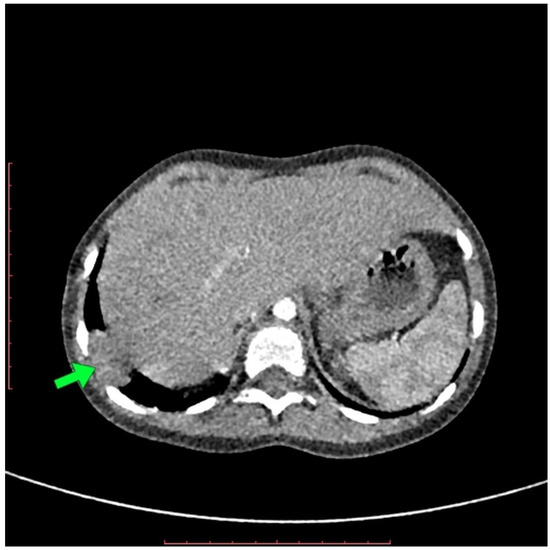

| Four years and two months old | The CT scan of thorax |